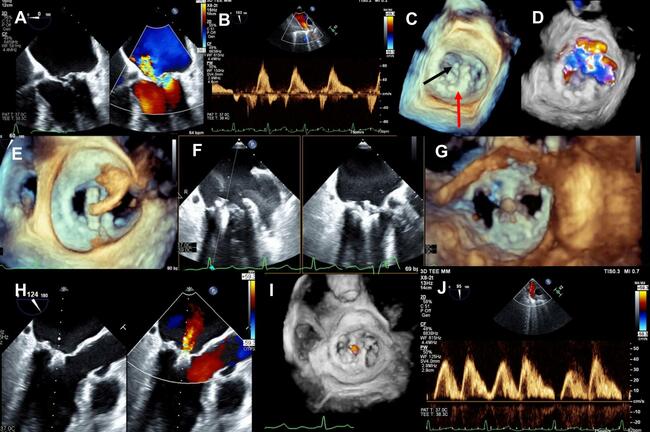

A transthoracic echocardiogram (TTE) revealed moderately reduced left ventricular systolic function and severe eccentric MR with a mean gradient of 3 mm Hg. Further evaluation using transesophageal echocardiography (TOE) demonstrated posterior leaflet flail with severe anteromedially directed MR (Figure A, Video 1) and systolic flow reversal in the pulmonary veins (Figure B). Three-dimensional views revealed the ring attached to the lateral annulus (Figure C, red arrow), the flail segment (Figure C [black arrow], Video 2), and the associated MR (Figure D, Video 3).

Treatment options were discussed at a multidisciplinary team meeting. Despite reasonable low surgical risk for reoperation, the patient declined the surgical procedure. He was subsequently offered mitral transcatheter edge-to-edge repair (TEER), which he accepted. Atrial transseptal puncture was performed superiorly and posteriorly under TOE supervision and guidance. Through the delivery sheath, a MitraClip (Abbott) was advanced into the left ventricle through the mitral ring after appropriate positioning (Figure E, Video 4). Alignment and perpendicularity were confirmed, and the leaflets were successfully grasped (Figure F, Video 5). TOE evaluation revealed adequate grasp of both mitral leaflets (Figure G, Video 6), mild residual MR (Figure H and I, Videos 7 and 8), improvement in systolic antegrade pulmonary vein Doppler velocities (Figure J), and a final gradient of 3 mm Hg.